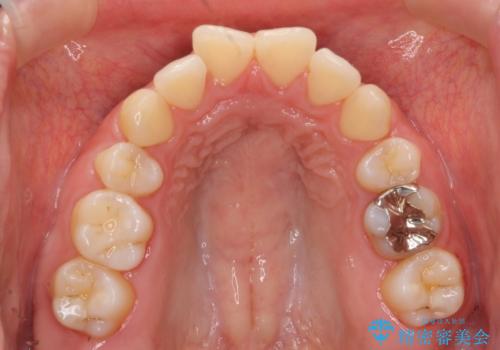

生まれつき下顎の前歯が3本でした。(本来は4本)。上の前歯をそのまま並べると出っ歯になってしまうのでディスキングを行い、上下の前歯がかむようにしました。

また、左上第二大臼歯が頬側転位していたのも治しました。